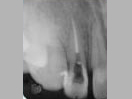

X-ray

Pre-Operation

After 3 months

x-ray post operation

After 2 years